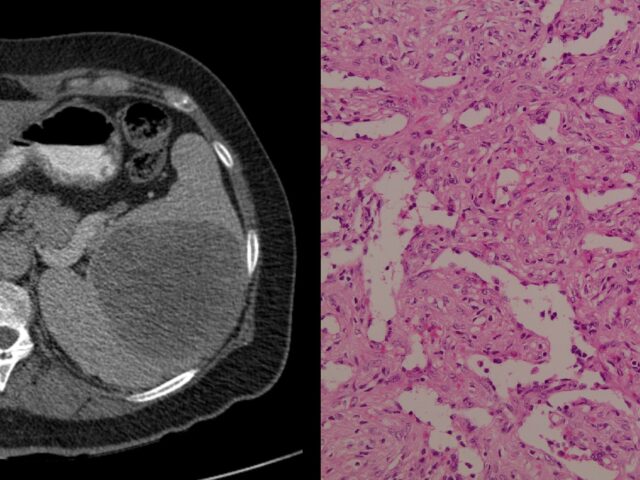

Η εργασία ”Sclerosing angiomatoid nodular transformation of the spleen presenting with declining hematocrit: a case report and review of the literature”, δημοσιεύτηκε στο Journal of Surgical Case Reports. Περιγράφει μία εξαιρετικά σπάνια καλοήθη αγγειακή βλάβη του σπληνός. Παρουσιάστηκε σε ελληνικά και διεθνή συνέδρια – forum: – 16ο Πανελλήνιο συνέδριο Λαπαροσκοπικής και Ρομποτικής Χειρουργικής, Αθήνα, 30/05 […]

Η εργασία παρουσιάστηκε στο 34ο Πανελλήνιο συνέδριο Χειρουργικής που έλαβε χώρα στην Αθήνα στις 19-23 Νοεμβρίου 2025. Σκοπός της εργασίας είναι η παρουσίαση ενός εξαιρετικά σπάνιου περιστατικού και η ανασκόπηση της βιβλιογραφίας για τη Σκληρυντική Αγγειοματώδη Οζώδη Μετατροπή του Σπληνός. Πρόκειται για σπάνια καλοήθη αγγειακή βλάβη αβέβαιης αιτιολογίας που προέρχεται από τον κόκκινο πολφό. Η […]